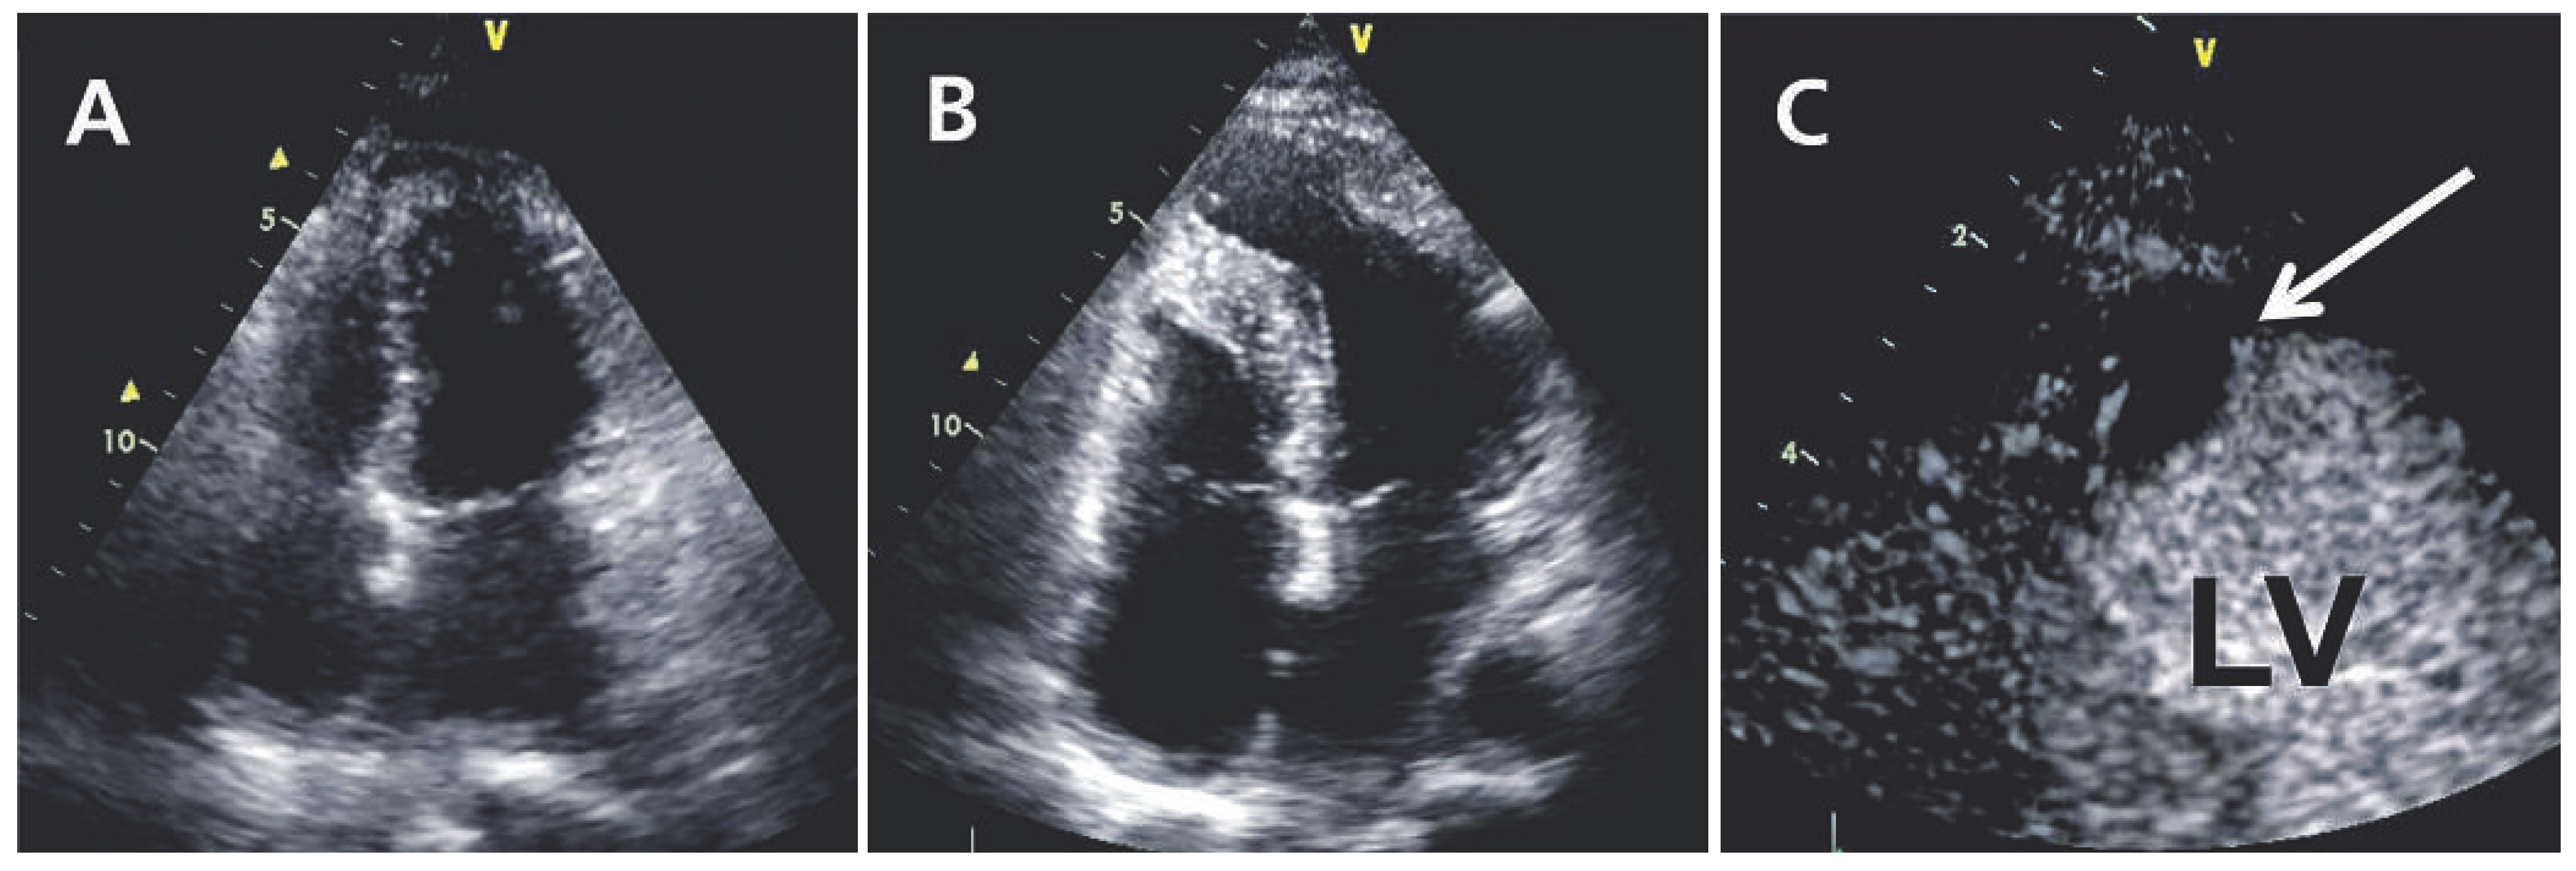

Left Ventricular Apical Thrombus Many Months After Pericardial Biopsy